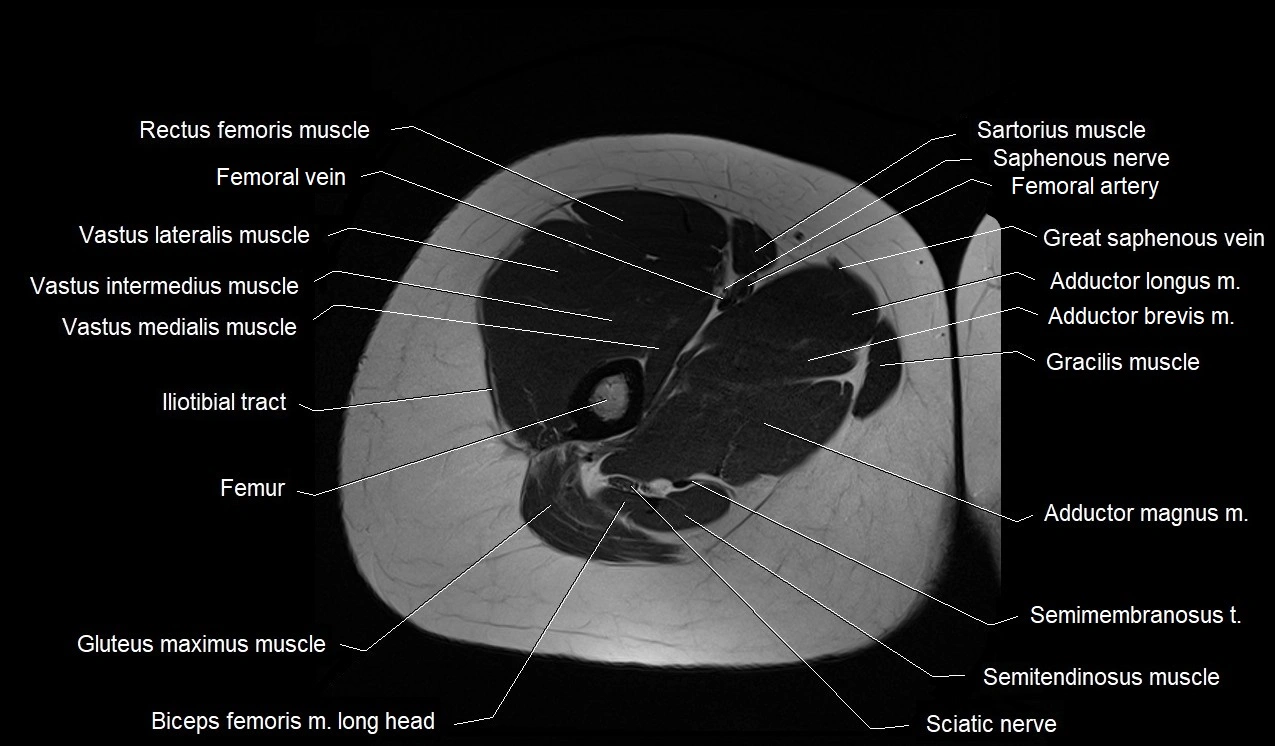

- Adductor brevis muscle

- Adductor longus muscle

- Adductor magnus muscle

- Biceps femoris muscle (Long head)

- Femoral artery

- Femoral vein

- Femur

- Gluteus maximus muscle

- Gracilis muscle

- Iliotibial tract

- Rectus femoris muscle

- Sartorius muscle

- Semimembranosus muscle

- Semitendinosus muscle

- Tibial nerve

- Vastus intermedius muscle

- Vastus lateralis muscle

- Vastus medialis muscle